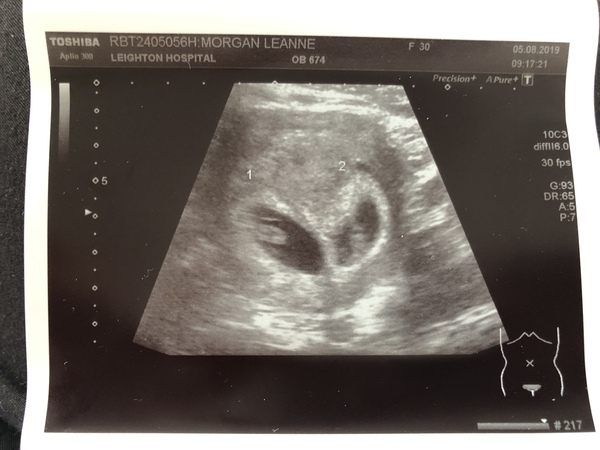

We’re having TWINS!!!! 😱😱😱❤️❤️❤️❤️

Both 2 beautiful heartbeats measuring at 7+2, separate sacs also and non identical twins xx

Lea89 · 05/08/2019 15:41

Here is the scan... ❤️❤️

Aww very exciting @Lea89. I think that's allowed 😊 When's your next scan? Your scan is beautiful 😍

@Lea89 I'm sorry I can't help but laugh! I think it's bloody fantastic! Double trouble but double the love 🥰🤰❤️! No matter how many kids you have you just do it that's what is mum's do so don't you worry! It's amazing I'm a little bit envious haha!! Oh god @VenusStarr imagine.... That would be the 2 first people I spoke to on Mumsnet and the only 2 that have continued to keep contact pregnant with twins!! Im super excited for your scan 😬, do you know when it will be? Lea, Venus is right your scan is so beautifu. It looks like a wee loveheart ❤️xx